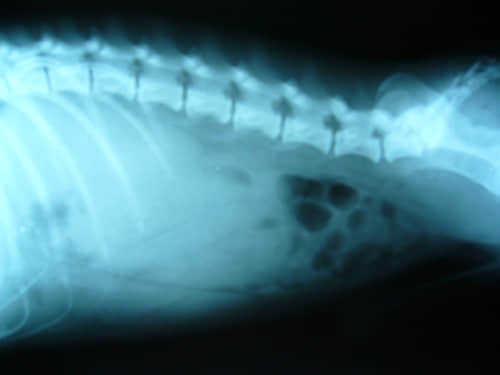

图2、侧位平片

图2看到,在L1-L5的下方有一密度均匀的巨大灰色软组织阴影的影像,该影像前方和上方边界不清,后方与下方界限较清楚,从外型和位置来看此影像极有可能是肾脏。